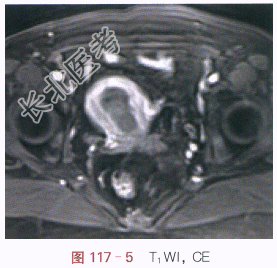

影像学资料如图117-1~图117-5所示。

读片分析:子宫稍增大,内膜弥漫性增厚,结合带中断。增强扫描后,增厚的内膜呈不规则强化,局部浸润超过肌层1/2厚度。